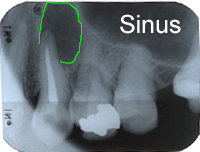

Im Röntgenbild von Abb. 3 ist ein gut erbsengrosses Granulom (Pfeil) an der Wurzelspitze eines toten, devitalen Zahnes feststellbar. Die Patientin wünschte die Erhaltung des Zahnes, zumal auch der vordere Nachbarzahn marktot und beherdet war. Abb. 4 zeigt das Röntgenbild nach der Wurzelfüllung.

Ein 59 Jahre alter Patient kommt als Neuaufnahme 2005 zum ersten Mal in unsere Praxis. Wir machen routinemässige Röntgenaufnahmen aller marktoten, devitalen (abgestorbenen) Zähne. Im Röntgenbild von Abb. 1 entdecken wir eine ca. kirschgrosse Kieferzyste im Oberkiefer (grün umrandet in Abb. 7). Eine Zyste ist grundsätzlich ein pathologischer Hohlraum, gefüllt mit einer Flüssigkeit. Die Zyste wächst und wird kontinuierlich grösser wegen Innendruckzunahme. Kieferzysten sind gutartig.

Die Ursache dieser Zyste liegt in einer insuffizienten Zahnwurzelbehandlung (siehe Endodontie). Die Zyste muss operativ entfernt werden.